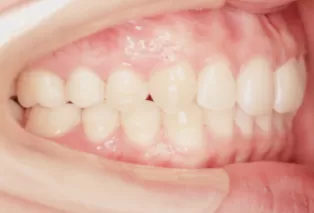

Photos intra-orales